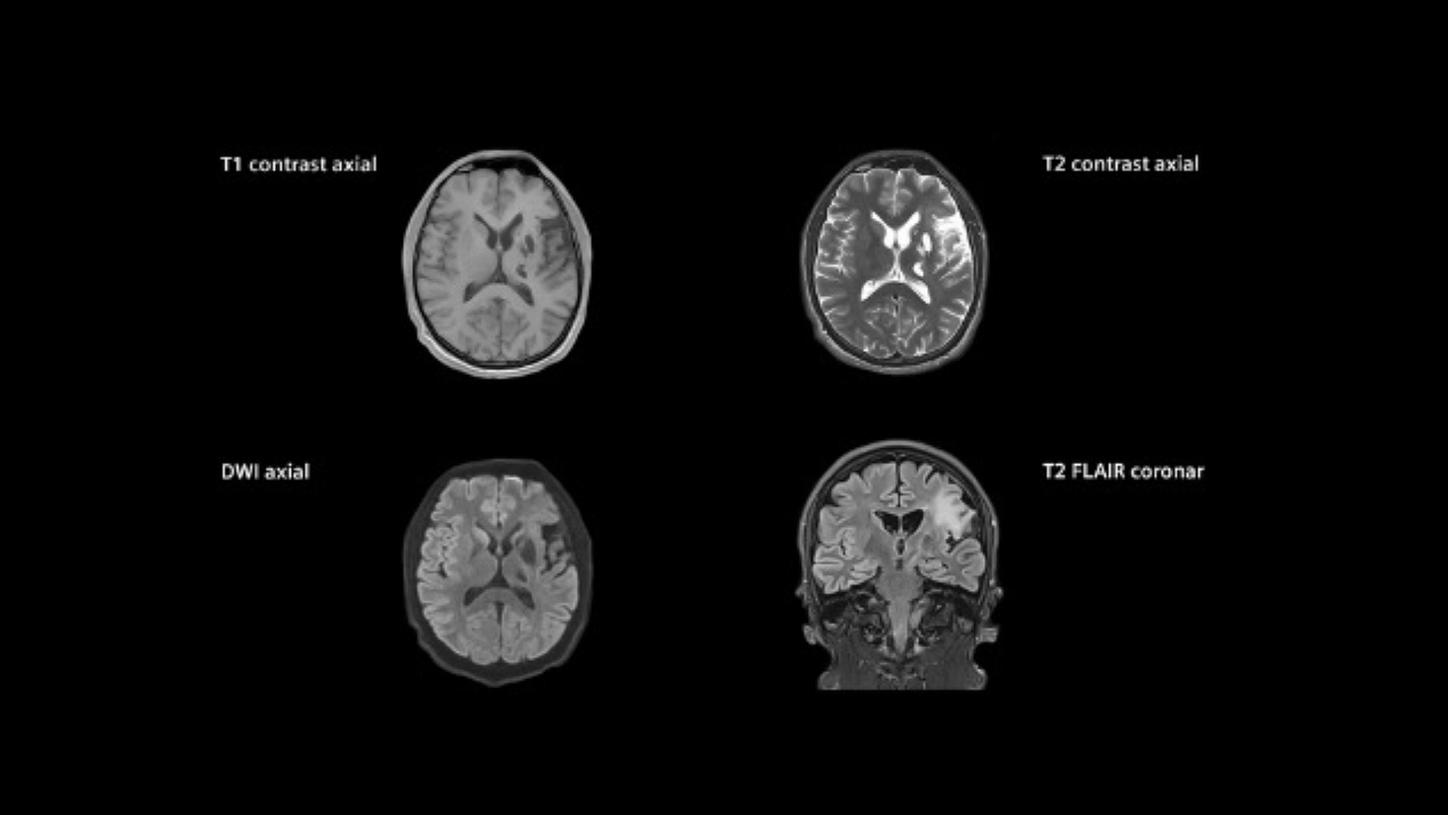

MAGNETOM Vida: Standard stroke protocol

MAGNETOM Vida: Standard stroke protocol

example of hemorrhage visualization

MAGNETOM Vida: Standard stroke protocol

example of hemorrhage visualization

The WAKE-UP trial shows favorable outcomes for acute ischemic stroke patients with an unknown stroke onset: Patients identified by DWI-FLAIR mismatch on MRI with subsequent thrombolysis had significantly better functional outcomes than the placebo group.7

The WAKE-UP trial shows favorable outcomes for acute ischemic stroke patients with an unknown stroke onset: Patients identified by DWI-FLAIR mismatch on MRI with subsequent thrombolysis had significantly better functional outcomes than the placebo group.7

The WAKE-UP trial shows favorable outcomes for acute ischemic stroke patients with an unknown stroke onset: Patients identified by DWI-FLAIR mismatch on MRI with subsequent thrombolysis had significantly better functional outcomes than the placebo group.7